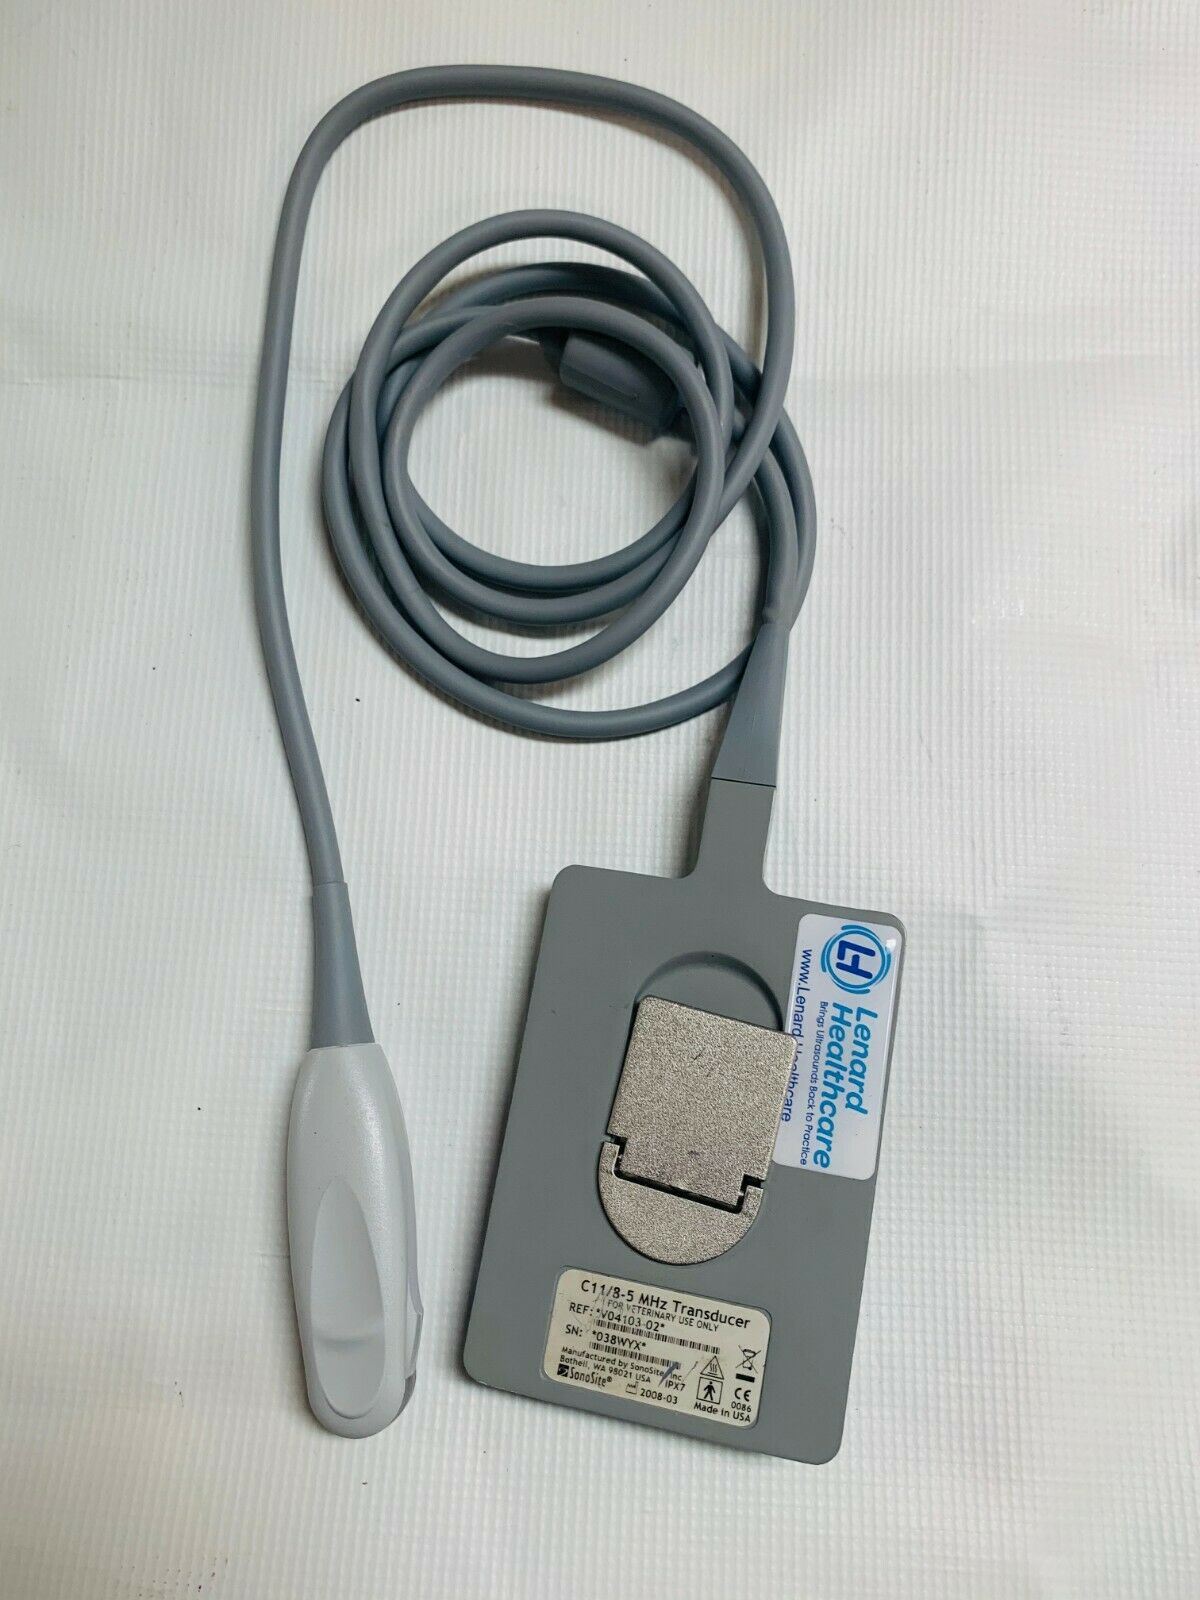

Veterinary Micro convex probe C11 8-5Mhz For Sonosite portable ultrasounds 2008

Sale price$ 1,639.18

Regular price$ 1,999.00